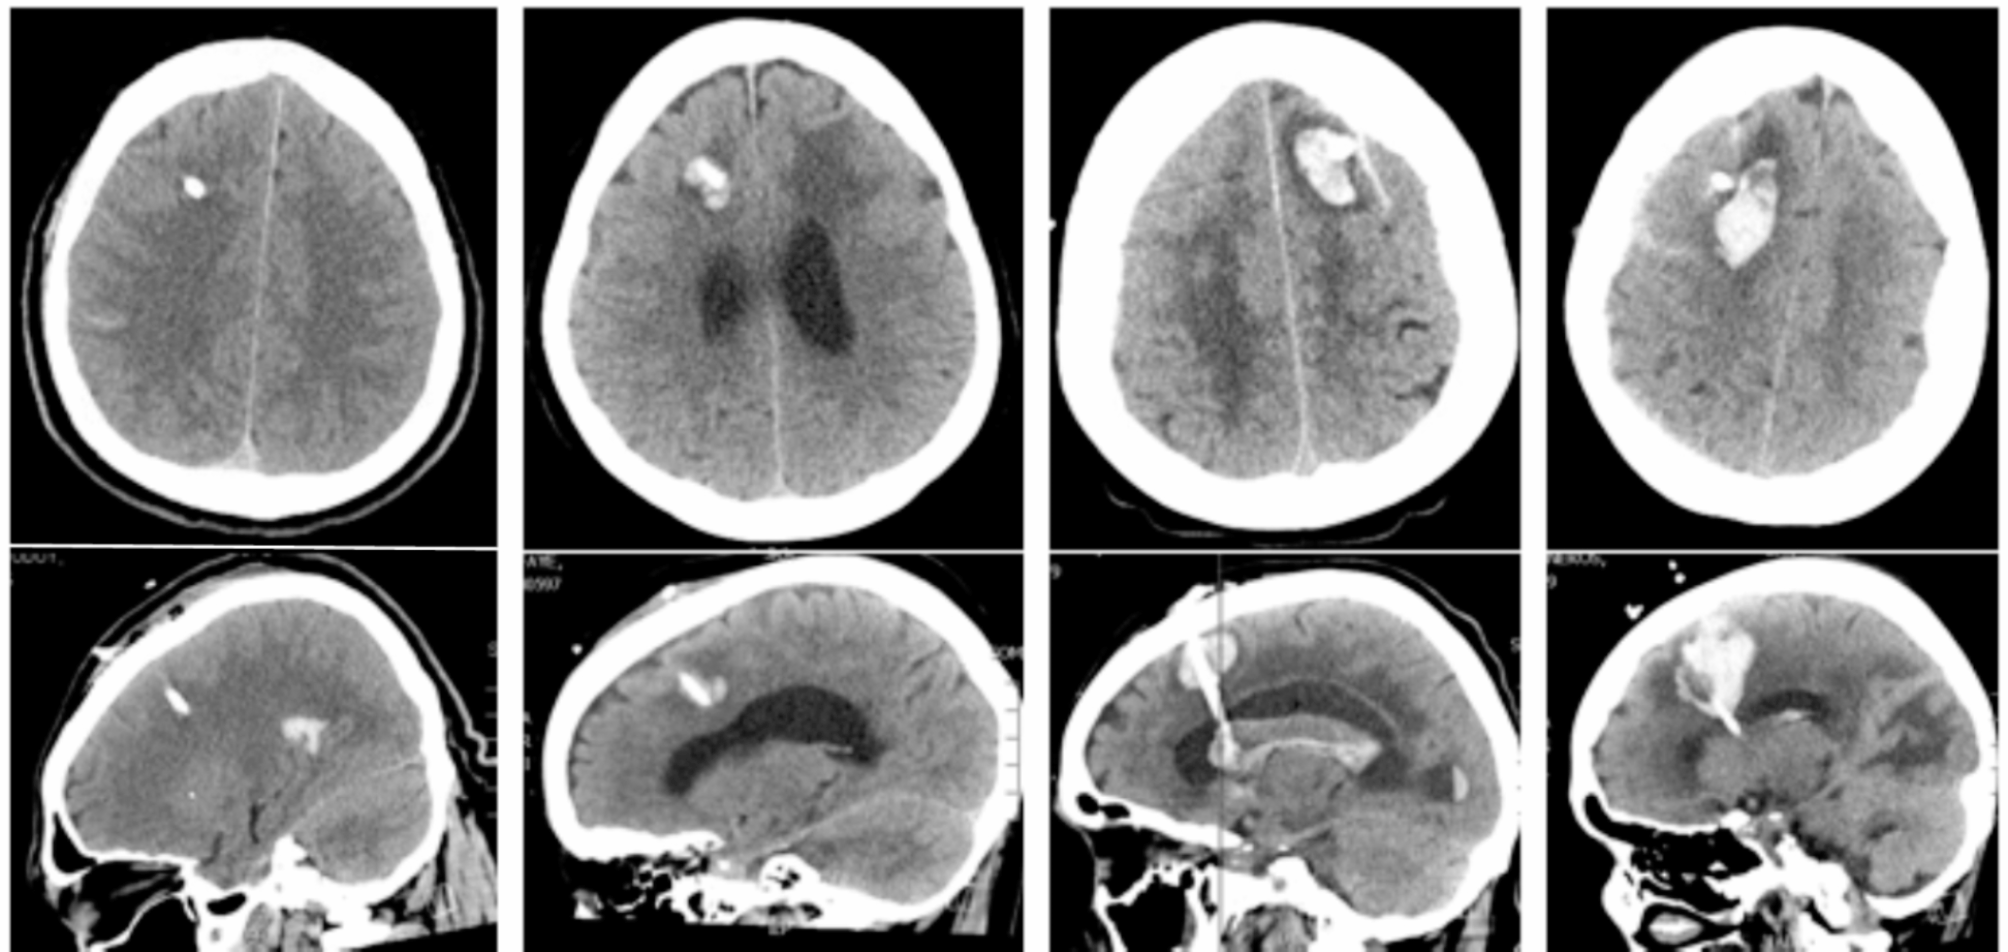

Fig. 1

Axial (top) and sagittal (bottom) computed tomography images of the brain showing (A) grade 0 no hemorrhage, (B) grade 1 hemorrhage, (C) grade 2 hemorrhage, and (D) grade 3 hemorrhage.